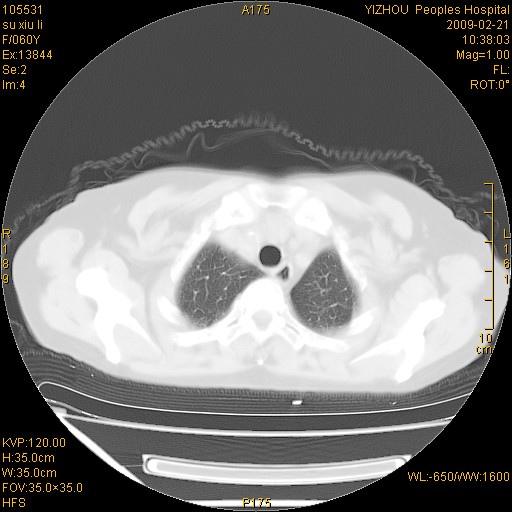

标题: CT18259:两肺间质纤维化? [打印本页]

标题: CT18259:两肺间质纤维化?

女,60岁,反复咳嗽1月。

两肺支扩,以肺为著合并双肺较广范纤维化病变。建议除外结核等病变。

间质性肺炎

符合间质感染,部分纤维化表现

特发性间质纤维化

特发性间质纤维化伴支扩!